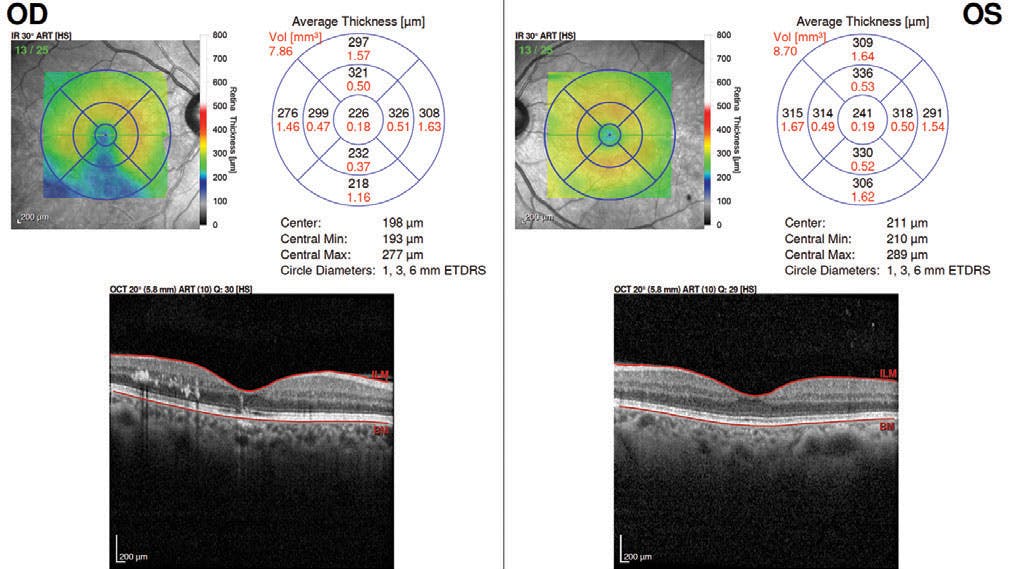

At the 2-week follow-up, the patient’s VA had recovered to 20/20 OS. OCT of his left eye showed a disorder of the retinal pigment epithelium cells in the damaged area, with no signs of macular edema (Figures 3 and 4). Retinography revealed a resorbing lower temporal vitreous hemorrhage and a retinal hemorrhage that had already reabsorbed.